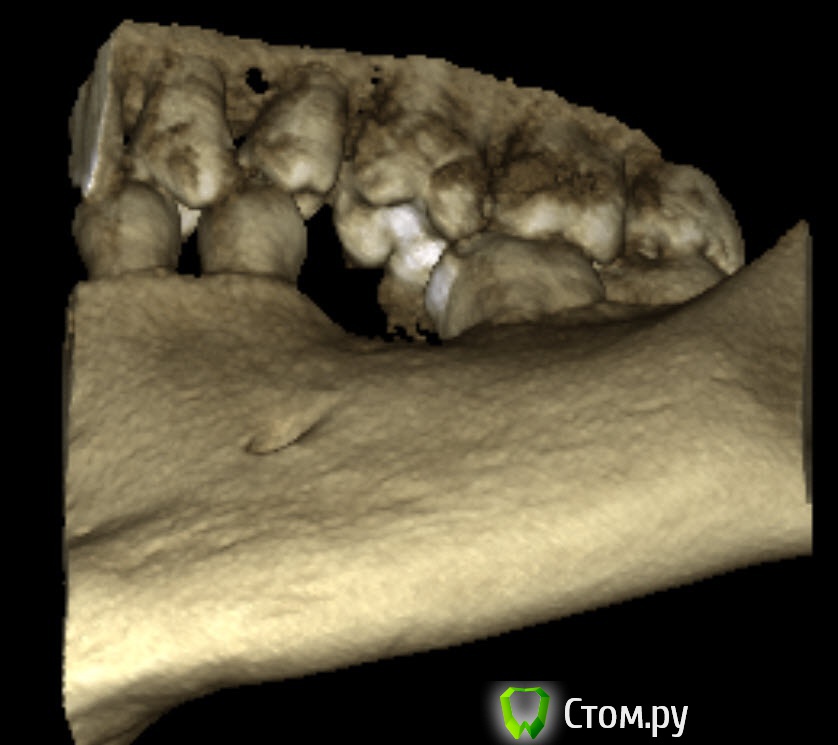

bobrdobr Опубликовано 5 февраля, 2014 Автор Поделиться Опубликовано 5 февраля, 2014 Огромное спасибо всем докторам, кто отписывается в теме. Сегодня история получила неожиданное продолжение. Побывал на очном приеме Хирурга 3. Cтавит Xive и Bicon. К моему удивлению, он однозначно предложил мне Bicon. Аргументы за Bicon такие (пишу по памяти, возможны неточности!):За время отсутствия зуба кость ушла на 1-2 мм. Винтовой имплант (в т.ч. Xive) в моей ситуации требует укрепления костной стенки остеопластическим материалом с мембраной. Без костной пластики поставить можно, но стенка будет тонкой и воспаление под десной - дело времениBicon позволяет обойтись без костной пластики в моем случаеУ Bicon коронка и абатмент соединяются цементом в руках, а не во рту, подтекание цемента исключеноУ Bicon герметичное внутреннее конусное соединениеУ Bicon абатмент имеет выраженную шейку и ее можно дофрезеровать, учитывая размеры основания коронки и особенности десны. У винтовых имплантов абатмент внутри, а на жевательном зубе винт всегда уже чем коронка, поэтому соединение коронка-имплант получается менее анатомичным.При необходимости можно вынимать абатмент с коронкой и ставить обратноБыли озвучены такие "минусы" BiconНе подходят для передних зубов и клыков, вываливаются из-за наличия "боковой" нагрузки. Но у меня 46, так что будто бы все в порядке.Дают небольшую усадку, поэтому коронка ставится выше на пару мм. Жевать в первое время может быть не очень удобноОтзывы о Bicon на форуме не радуют. К моему удивлению, ортопед, работающий в паре с Хирургом 3, положительно отнесся к Bicon. Говорит, что ему протезировать на Bicon даже удобнее, чем на Xive. Хирург 2 также имеет в арсенале Bicon, но мне на консультации предложил винтовой Semados. Посчитал ненужной пластику? Основная его претензия к Bicon: сложность точного позиционирования из-за установки "заколачиванием". Буду рад услышать ваши ценные указания . Прикладываю свежий панорамный снимок. А еще лучше найдите ортопеда и идите к тому хирургу, которого он посоветует. Хорошая идея, спасибо! Еще как минимум к одному хирургу хочу попасть, чтобы прояснить вопрос с костной пластикой. Ссылка на комментарий

bobrdobr Опубликовано 17 февраля, 2014 Автор Поделиться Опубликовано 17 февраля, 2014 Добрый всем день. Сделал КТ. Снимок выложил на Яндекс.Дискhttp://yadi.sk/d/-CHDNu-nJ45Wy Посмотрите пожалуйста. Вопрос прежний: нужна ли костная пластика в каком-то виде перед установкой винтового импланта? Ссылка на комментарий

bobrdobr Опубликовано 17 февраля, 2014 Автор Поделиться Опубликовано 17 февраля, 2014 Хорошо. Так подойдет? Ссылка на комментарий

Bier Опубликовано 17 февраля, 2014 Поделиться Опубликовано 17 февраля, 2014 судя по фото, скорее всего нужна. От КТ нужен срез горизонтальной плоскости - вид сверху на костный гребень, на 1 мм ниже его вершины. Ссылка на комментарий

bobrdobr Опубликовано 18 февраля, 2014 Автор Поделиться Опубликовано 18 февраля, 2014 (изменено) Имплант был предложен Semados 4,1*11,5 без костной пластики. судя по фото, скорее всего нужна. От КТ нужен срез горизонтальной плоскости - вид сверху на костный гребень, на 1 мм ниже его вершины. Сейчас попробую. Прикладываю 4 снимка: на уровне гребня (как мне кажется) и на 1,2,3 и мм. ниже. Изменено 18 февраля, 2014 пользователем bobrdobr Ссылка на комментарий

Bier Опубликовано 18 февраля, 2014 Поделиться Опубликовано 18 февраля, 2014 Можно поставить, одновременно добавив немного кости и закрыть мембраной. Кость можно даже взять прямо из того места, куда будет ставиться имплантат, т.е. доп травмы не будет Ссылка на комментарий